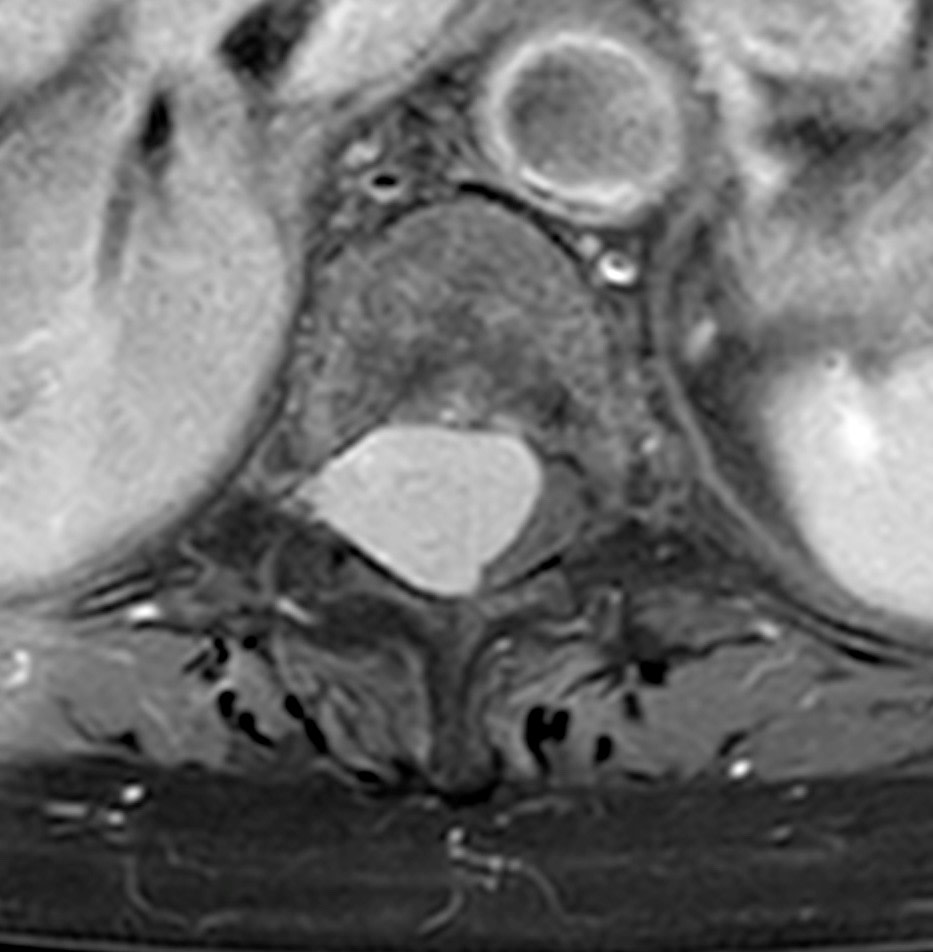

Les tumeurs intra-durales, situées à l’intérieur du sac méningé qui renferme le système nerveux central, représentent un défi médical majeur. Les principaux types de tumeurs affectant cette zone sont les méningiomes et les neurinomes, nécessitant une expertise neurochirurgicale de haut niveau. La chirurgie intra-durale rachidienne est reconnue pour sa complexité et ses risques élevés, exigeant la présence de deux neurochirurgiens, un microscope opératoire et des instruments de microchirurgie.

Cette avancée permet désormais de réaliser des chirurgies intra-durales des tumeurs thoraciques et lombaires à Narbonne, offrant ainsi aux patients une prise en charge locale et évitant les déplacements hors de la région.